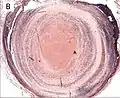

| A recent pulmonary thrombo-embolus with prominent lines of Zahn. The pale areas consist of fibrin and platelets. The red areas consist of erythrocytes. | |

Thrombus showing circumferential lines of Zahn.

Thrombus showing circumferential lines of Zahn. Low magnification micrograph showing laminations in a thrombus in a fatal pulmonary embolism. H&E stain.